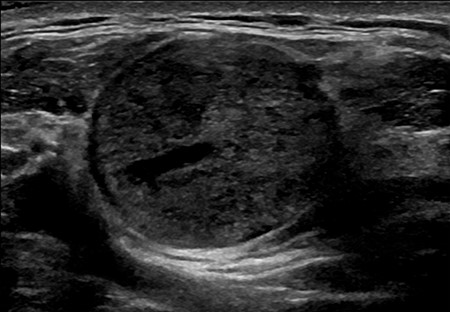

Routine blood tests showed no abnormalities and his tumour markers were normal. A neck ultrasound demonstrated a heterogeneous solid mass with marked internal vascularity located within the base of the right neck (Fig. 1). It was closely associated with SCM but remained external to the carotid and visceral space. A computed tomography (CT) scan of the neck concurred with the ultrasound findings, suggestive of a suspicious well-circumscribed hypervascular mass within the right supraclavicular fossa at the origin of SCM (Fig. 2).

An ultrasound image of the well-circumscribed 22 × 22 × 25 mm round solid mass, which is located within the right supraclavicular fossa and intimately associated with the sternocleidomastoid muscle at its origin. The lesion demonstrates marked internal vascularity and is superficial to the carotid and visceral space.